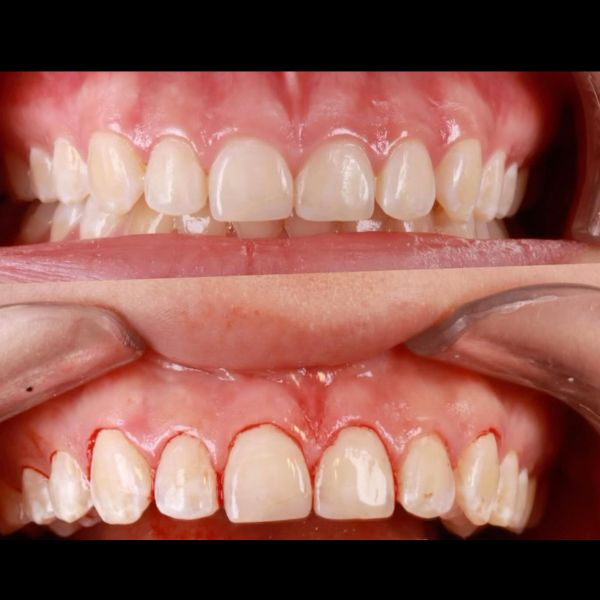

Dentica by Cristina Suaza

Odontólogo Bogotá

Antes y después de un recorte de encías para alargar los dientes y mejorar la armonía de la sonrisa, realizado en D…